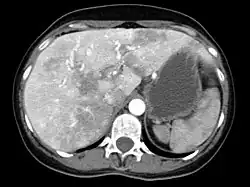

Liver AVMs may be suspected because of abnormal liver function tests in the blood, because the symptoms of heart failure develop, or because of jaundice or other symptoms of liver dysfunction. The most reliable initial screening test is Doppler ultrasonography of the liver; this has a very high sensitivity for identifying vascular lesions in the liver. If necessary, contrast-enhanced CT may be used to further characterize AVMs.[1][2][6] It is extremely common to find incidental nodules on liver scans, most commonly due to focal nodular hyperplasia (FNH), as these are a hundredfold times more common in HHT compared to the general population. FNH is regarded as harmless. Generally, tumor markers and additional imaging modalities are used to differentiate between FNH and malignant tumors of the liver. Liver biopsy is discouraged in people with HHT as the risk of hemorrhage from liver AVMs may be significant.[6][7] Liver scans may be useful if someone is suspected of HHT, but does not meet the criteria (see below) unless liver lesions can be demonstrated.[7]